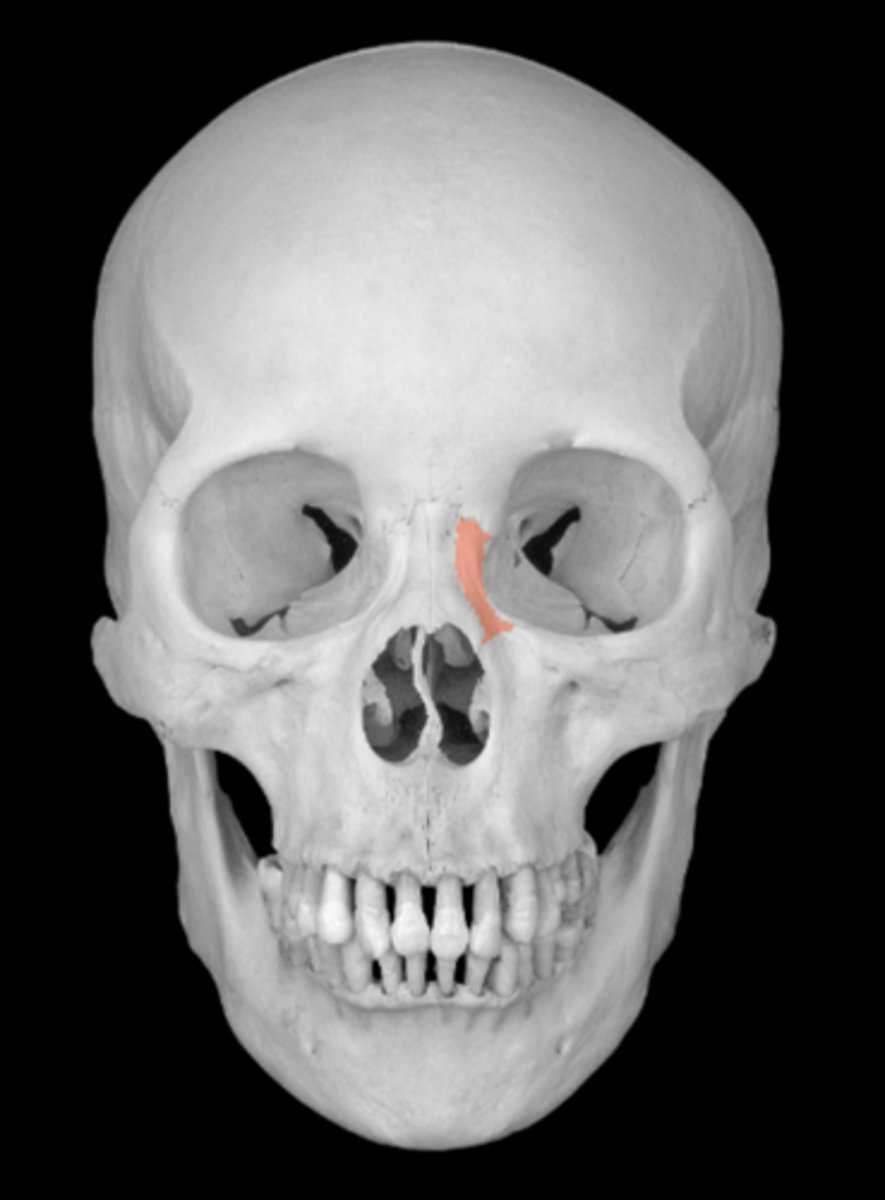

frontal process of the maxilla

lacrimal groove of maxilla

anterior lacrimal crest of maxilla